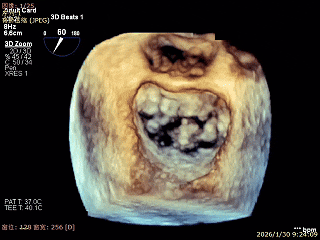

3D Enface 2区及3区前叶脱向左房

3D Enface 可见反流由2区3区从前后冲出

3D Enface下组织桥稳定残余外侧前叶脱垂

3D Enface上彩可见夹子内侧无反流,残余外侧反流

3D Enface下组织桥稳定无反流

夹子释放后,反流基本消失

LVOT切面可见主瓣二尖瓣术后反流基本消失